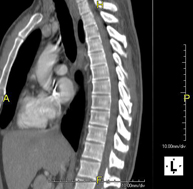

Prueba diagnóstica que consiste en obtener imágenes del tórax de alta definición anatómica (pulmones, corazón, mediastino, grandes vasos, caja torácica, etc.) mediante el empleo de un equipo de TC (Tomografía Computarizada). Dichas imágenes se estudian posteriormente en una estación de trabajo que permite reconstrucciones bidimendionales en diferentes planos del espacio y también reconstrucciones 3D (volumétricas). Algunos estudios requieren el empleo de contraste yodado para mejorar la definición de las imágenes. - Angio-TC Aorta torácica

Prueba diagnóstica que consiste en el estudio de la aorta torácica (principal arteria del tórax) mediante el empleo de un equipo de TC (Tomografía Computarizada). Esta técnica requiere el empleo de contraste yodado, y proporciona imágenes de alta definición anatómica. El uso del TCMD (TC Multidetector) acorta el tiempo de exploración, disminuye la dosis de radiación y mejora la calidad de la imagen. Gracias a los múltiples detectores, en determinados estudios se puede acoplar la obtención de la imagen con el latido cardíaco, técnica que permite el estudio de la válvula aórtica y de la raíz de la arteria aorta (primeros centímetros), donde el latido del corazón suele provocar múltiples artefactos de movimiento. - Angio –TC Artèries pulmonars (estudi TEP, Tromboembòlia pulmonar)